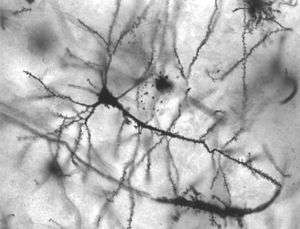

| Neurons in person with epilepsy, 40x magnified. | |